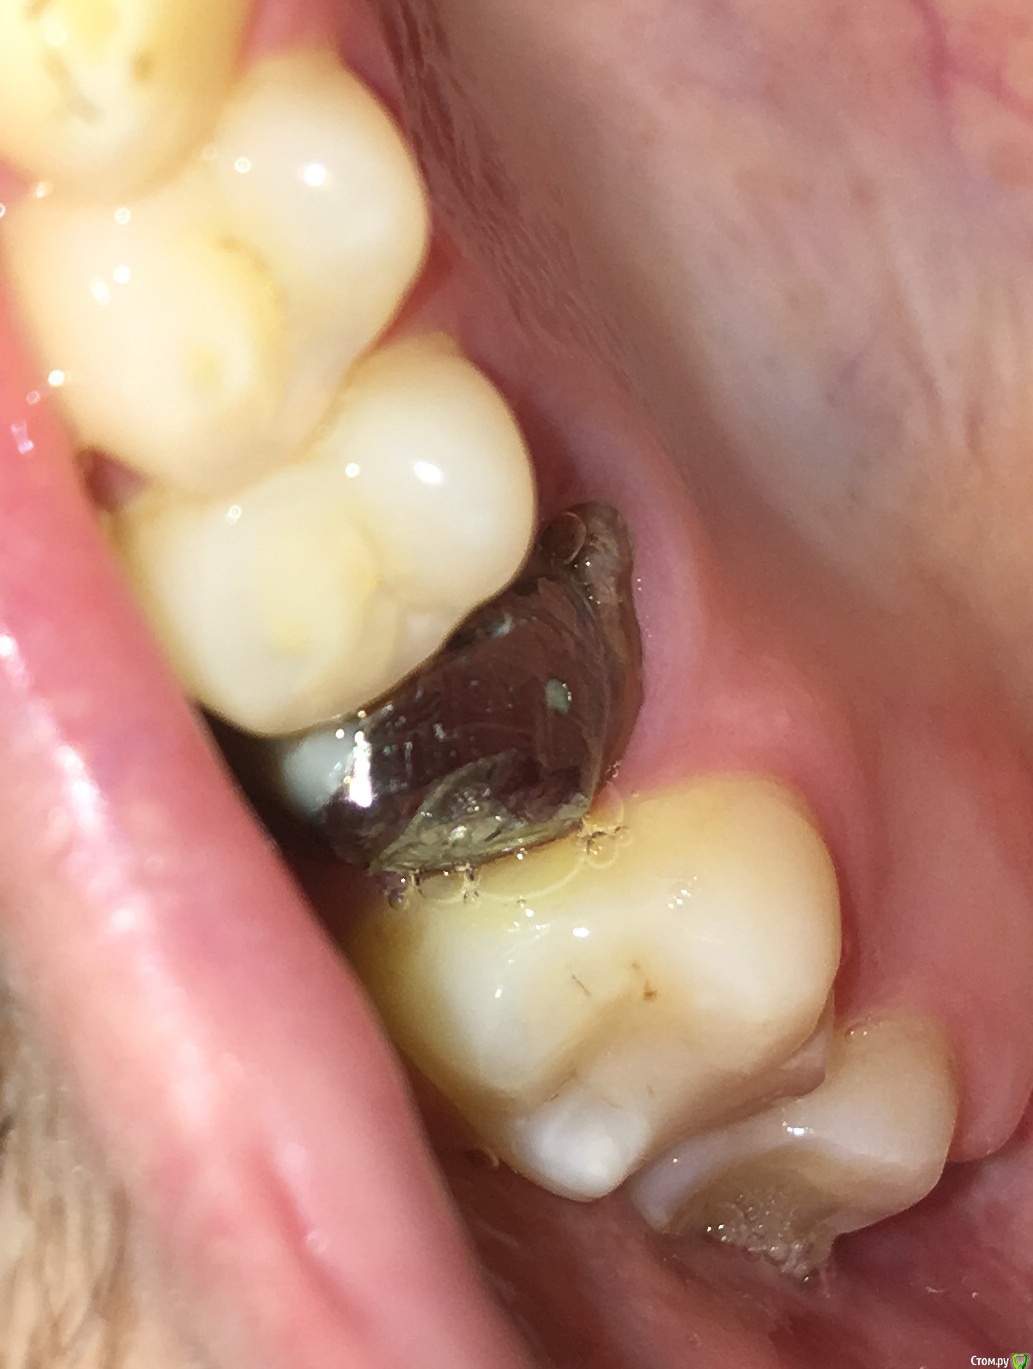

MichaelV Опубликовано 17 октября, 2019 Автор Поделиться Опубликовано 17 октября, 2019 (изменено) Вот какая ситуация на сегодня.Забыл сказать, что в прошлый прием (неделю назад, когда я написал этот пост), мне немного подточили опорный зуб (возможно и часть вкладки, но не уверен) около десны. Изменено 17 октября, 2019 пользователем MichaelV Ссылка на комментарий

chervoncevdaniil Опубликовано 17 октября, 2019 Поделиться Опубликовано 17 октября, 2019 Чуда не произошло 1 Ссылка на комментарий

MichaelV Опубликовано 10 ноября, 2019 Автор Поделиться Опубликовано 10 ноября, 2019 (изменено) Сняли повторный слепок с ниткой, сделали новую коронку, выглядит так: https://cloud.mail.ru/public/8RrK/2uRCNHkwp (выложил несколько фото в облако, т.к. на форум больше одной уже не влезает). Изменено 10 ноября, 2019 пользователем MichaelV Ссылка на комментарий